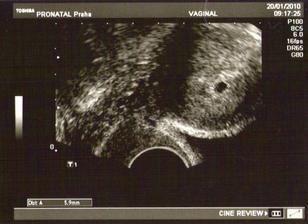

25. září čekáme miminko

Po jednou neúspěchu teď věříme v úspěch. Držte palce!